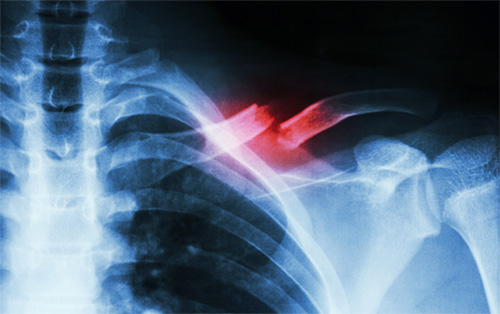

การแตกหักของกระดูไหปลาร้าเป็นไปได้หลายลักษณะ บางครั้งอาจหักทั้งชิ้น ซึ่งมักจะมีการเคลื่อนของกระดูกร่วมด้วย แต่บางครั้งไหปลาร้าที่หักนั้นก็ยังมีบางส่วนติดกันอยู่ หรือบางครั้งอาจแตกแบบละเอียด ซึ่งจะทำให้มีอาการปวด บวม ผิดรูป คนไข้ไม่สามารถยกแขนได้ หรือขยับแขนได้ลำบาก เพราะปวดมาก

เพราะกระดูกไหปลาร้า ทำหน้าที่เป็นเหมือนสะพานแขวนที่เชื่อมกระดูกสะบัก หัวไหล่ แขน และกระดูกส่วนกลางของลำตัวกับแขนไว้ด้วยกัน กล้ามเนื้อบริเวณรอบหัวไหล่ จึงต้องมีความยาวที่พอเหมาะกับสรีระร่างกายของแต่ละคน จึงจะทำให้มีแรงในการทำงาน มีแรงในการเคลื่อนไหว เมื่อกระดูกไหปลาร้าหัก จะทำให้กระดูกหรือกล้ามเนื้อหดสั้นลง แรงกำลังลดลง ไหล่ลู่หรืองุ้ม ทำให้ไม่มีแรงในการยกหรือขยับแขน